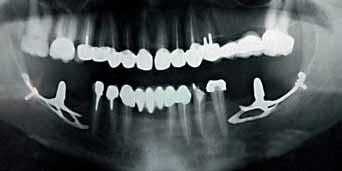

The dental literature on CBCT is promising and indicates that more research is required to explore the benefits of CBCT in forensic dentistry. Although no literature was found on prosthodontic applications of CBCT, the improved standard of care seen in prosthodontic treatment can be attributed to applications of CBCT found in other dental specialties and related to prosthodontic, such as bone grafting, soft tissue grafting, prosthetic-driven implant placement, maxillofacial prosthodontics and Temporomandibular joint disorders. CBCT images are important in special cases that require the assessment of restorability of multiple teeth (Fig. 7a to 7e).

plate; this image indicates the teeth to be extracted and the grafting site before implant placement.